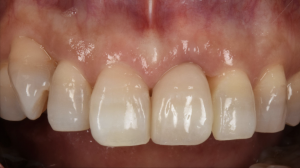

根が縦に割れてしまった前歯をインプラントで治療した症例【前歯部審美症例13】

初診時。前歯の歯茎が常に腫れていて痛いとのことでご来院されました。神経処置後の歯は破折のリスクが高くなってしまいます。レントゲン写真、CTで調べてみると被せものの下の根っこが縦に割れてしまっていること…